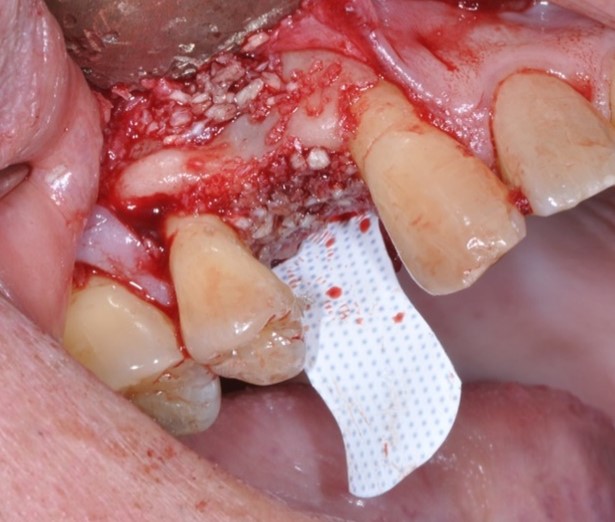

Barrier membranes exclude surrounding, faster growing epithelium cells from populating an extraction socket allowing bone remodeling, deposition, and maturation. The addition of bone augmentation material acts as an osteo-inductive and/or osteo-conductive scaffold. Angiogenesis of new blood vessels into the site promote introduction of osteoprogenitor cells. These osteoblasts and osteoclasts utilize the mineral components of the graft material to deposit organized, osseous architecture over a period of three to six months. Angiogenesis can be enhanced with decortication of the existing bony architecture allowing enhanced bulk and density, a principle called “regional acceleratory phenomenon”.

Figure Legend: A 38 y.o. white male patient presented with a chief complaint of persisting pain in the upper right area, ( tooth #5) for days. Diagnosis was endodontic lesion with a hopeless prognosis (Figure 1, 2). The tooth was extracted and Regional Acceleratory Phenomena performed (Figure 3), grafted with Allograft and Resorbable membrane (Figure 4 &5) employed for Guided Bone Regeneration (GBR) and sutured (Figure 6). Four months post Extraction and Ridge Preservation surgery (Figures 7 and 8, Implant was placed (Figure 9) to be restored after osseointegration period.